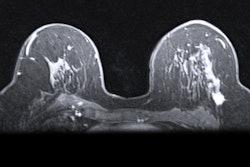

Curve-shaped breast compression paddles may lead to some pain relief, but they also reduce image quality on mammograms, suggest findings published August 20 in Radiology.

Researchers led by Daniëlle van der Waal, PhD, from the Dutch Expert Centre for Screening in Nijmegen, the Netherlands found that, compared with standard mammography compression paddles, curved paddles led to slight decreases in pain scores as reported by female patients. But the paddles also decreased image contrast and the visibility of structures.

However, the radiologists and radiographers differed in preference when it came to image quality. The two radiographers showed agreement for preference toward the standard paddle for craniocaudal images when it came to imaging the pectoral muscle and having better contrast in dark areas. On mediolateral oblique images, they preferred the standard paddle for the following criteria: pectoral muscle deeper, better depiction of area around the nipple, nipple in profile, better contrast in light areas, and better contrast in dark areas.

Among the two radiologists, there was only agreement on a significant preference for the standard paddle for better contrast in light areas on both craniocaudal and mediolateral oblique images. The researchers also noted no significant preference for the curved paddle for any of the criteria for the four observers.